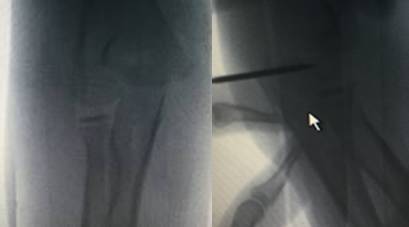

6 岁患者发生 Monteggia 骨折,肘关节造影术术中前后位透视可见经闭合复位后的桡骨颈骨折(白色箭头)和尺骨鹰嘴骨折

7 岁患者发生桡骨颈移位性骨折,肘关节造影术术中前后位透视可见关节线,并可帮助骨折获得满意复位(造影相关文字及图片摘引:Nowicki 关节造影术在小儿骨科的应用.林超文译)